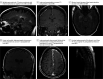

Figures